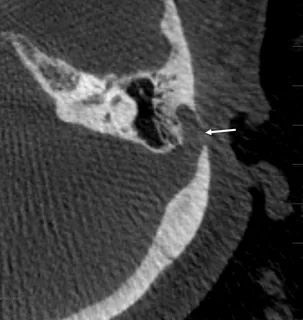

Venous Sinus Diverticula

A venous sinus diverticulum is a small outpouching of a venous sinus wall, frequently located near the ear at the junction of the transverse and sigmoid sinuses. These diverticula create turbulent blood flow that patients perceive as pulsatile tinnitus. While not dangerous, the symptoms can be severely debilitating and impact quality of life. Dr. Choudhri has published the clinical outcomes of endovascular treatment for venous sinus diverticula—one of the first outcome series in the literature for this condition—demonstrating high rates of symptom resolution.

Endovascular Coiling of Venous Diverticula

Venous sinus diverticula causing pulsatile tinnitus can be treated by placing coils within the outpouching to eliminate the turbulent blood flow that produces the sound. This targeted endovascular approach can resolve the tinnitus while preserving normal sinus flow.